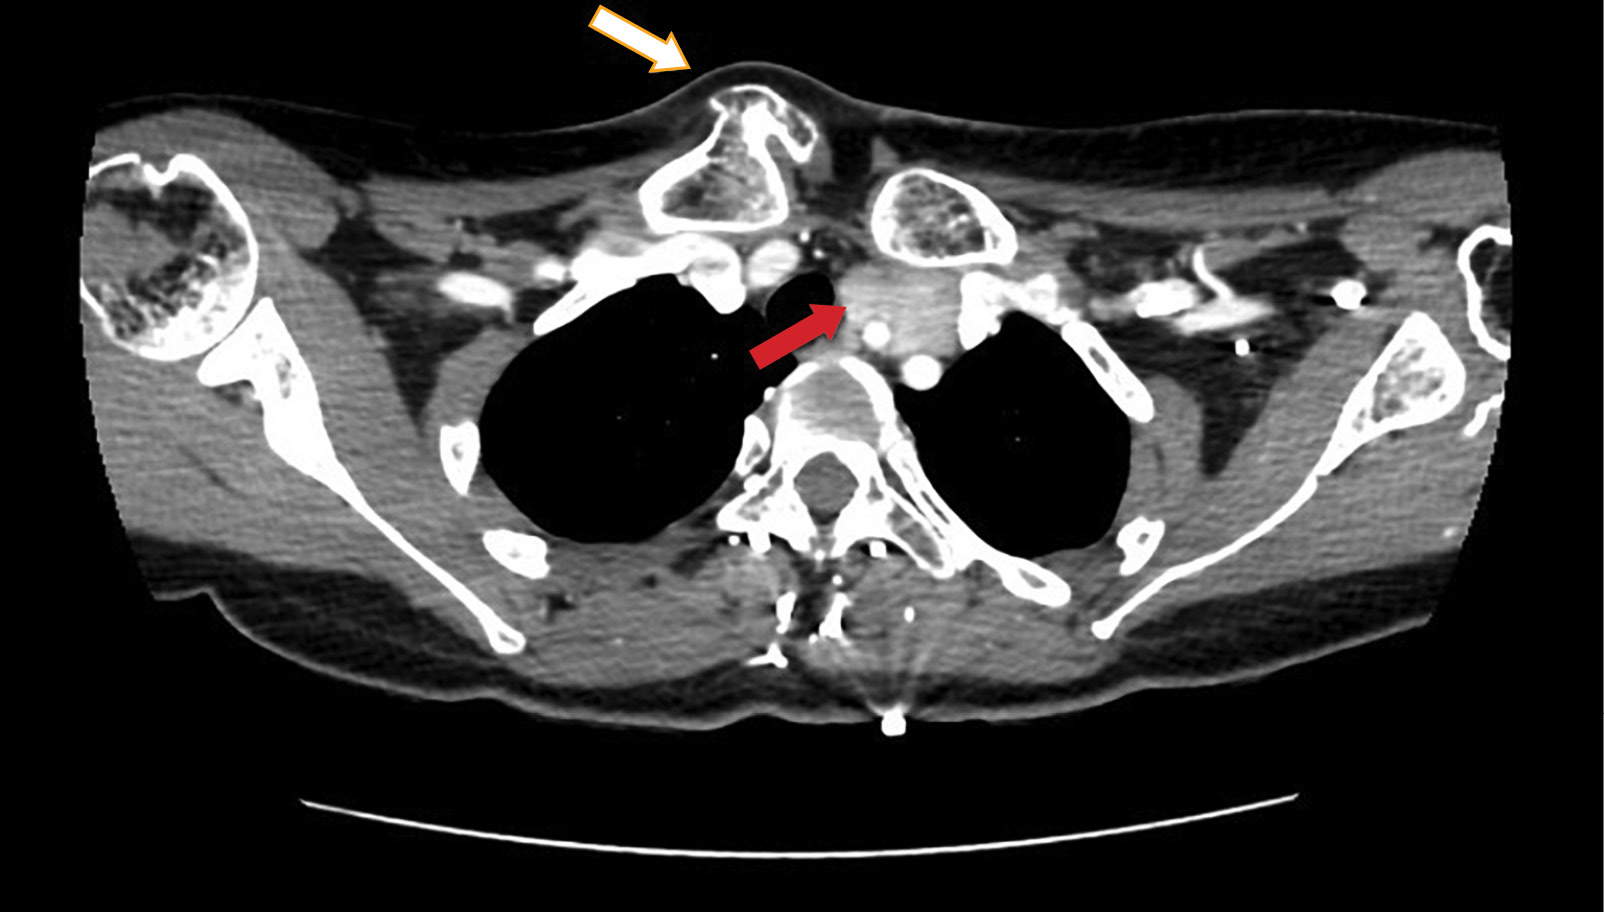

Рисунок 3. Диффузионная магнитно-резонансная томография шеи (красными стрелками указаны образования правой и левых околощитовидных желез).

3. Рисунок 3. Диффузионная магнитно-резонансная томография шеи (красными стрелками указаны образования правой и левых околощитовидных желез). | |

В рамках первого этапа топической диагностики проведено ультразвуковое исследование (УЗИ). Слева за нижней третью щитовидной железы визуализировано образование пониженной эхогенности с ровными контурами 7,2×2,6×1,3 см, распространяющееся вниз и загрудинно, до дуги аорты, охватывающее общую сонную артерию. С учетом крупных размеров опухоли, значимых изменений лабораторных показателей и тяжести течения заболевания, нельзя было исключить злокачественный характер патологии. В качестве дополнительных инструментальных методов проведены сцинтиграфия с однофотонной эмиссионной компьютерной томографией (ОФЭКТ/КТ), МСКТ шеи с контрастным усилением и диффузионная магнитно-резонансная томография (МРТ). В результате выявлены 3 образования ОЩЖ, два из которых более 3 см в диаметре: левая верхняя 1,5×1,2×3,9 см, атипично расположенная левая нижняя 2,7×2,2×5,9 см; правая нижняя 0,7×0,4×1,6 см (рис. 1–3).